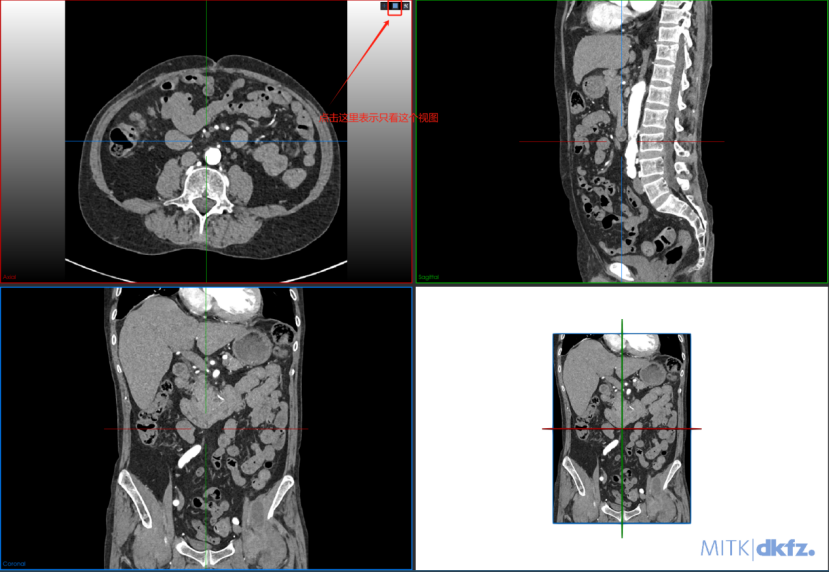

Step 4 进入一个窗口进行标注: 进入单个视图画面更大,更有利于标注。

如果标注完成也可退出此视图: